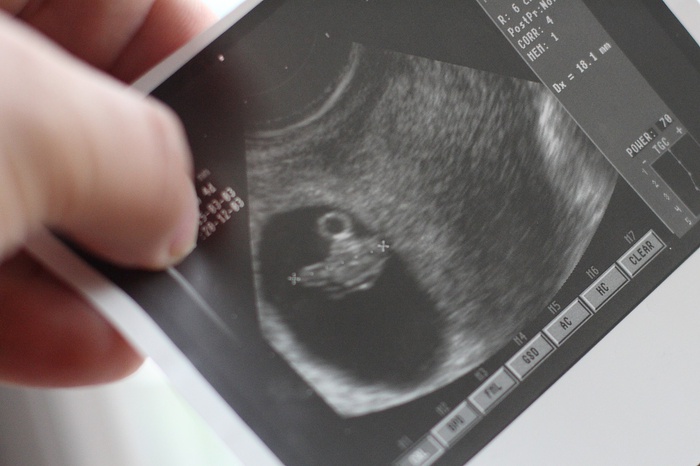

- Zapominamy, że płodność to ogromny dar. Jest oznaką zdrowia - bardzo czułym barometrem ogólnoustrojowego porządku, który powinien panować w organizmie - mówi dr n. med. Aleksandra Kicińska.

Fundacja prowadzi kampanię: "Czas na dziecko? - Naturalnie!", która ma uświadamiać społeczeństwu, że największym ryzykiem niepłodności jest późny wiek, a rodzicielstwo i rodzina to jeden z najpiękniejszych darów, jaki otrzymał człowiek. - Decyzja o założeniu rodziny została przesunięta daleko poza granice tej największej płodności, jaką podają podręczniki, czyli 20.-25. rok życia. Co nie oznacza, że nie udaje się nam pomóc nawet po 40. roku życia. Dysponujemy wiedzą i odpowiednimi narzędziami, by tę płodność przywracać - wyjaśnia dr Kicińska.

Interdyscyplinarne leczenie niepłodności w oparciu o biowskaźniki płodności może potrwać do 2 lat. - Kiedy robiłam podsumowanie badań z 4 lat pracy okazało się, że na ok. 400 leczonych osób u 40 proc. średnio po roku pojawiała się ciąża. Po 2 latach liczba ta wzrastała do 70 proc. Z tego urodziło się 85 proc. dzieci. Przy czym większość par zachodziła w ciążę po 11 miesiącach leczenia. To jest duży odsetek w porównaniu z metodami wspomaganego rozrodu - inseminacją czy in vitro. Tam odsetek jest niższy, a czas podobny - podkreśla dr Kicińska. Dodatkowo ogromną zaletą leczenia niepłodności proponowaną przez ośrodek leczenia niepłodności i zaburzeń cyklu miesięcznego "Invivo" jest możliwość naturalnego zajścia w kolejne ciąże.